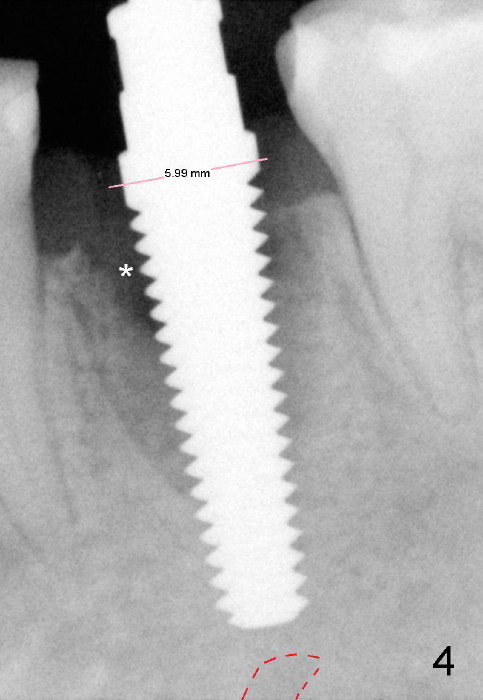

Taking multiple intraop X-ray is also necessary for depth adjustment (Fig.3-5).  For example, when a 5x20 mm tap is inserted at the depth of 17 mm, it is close to the mental loop (Fig.4), whereas the binding to the bone is minimal.  So a larger implant is to be placed at a shallower depth (Fig.5: 6x17 mm with insertion torque >60 Ncm).  The shallower implant placement creates limited space for future abutment and crown (Fig.6,7).  A short abutment will be used and the implant margin will be prepared as low as possible.  As expected, the wound heals in a week (Fig.8).